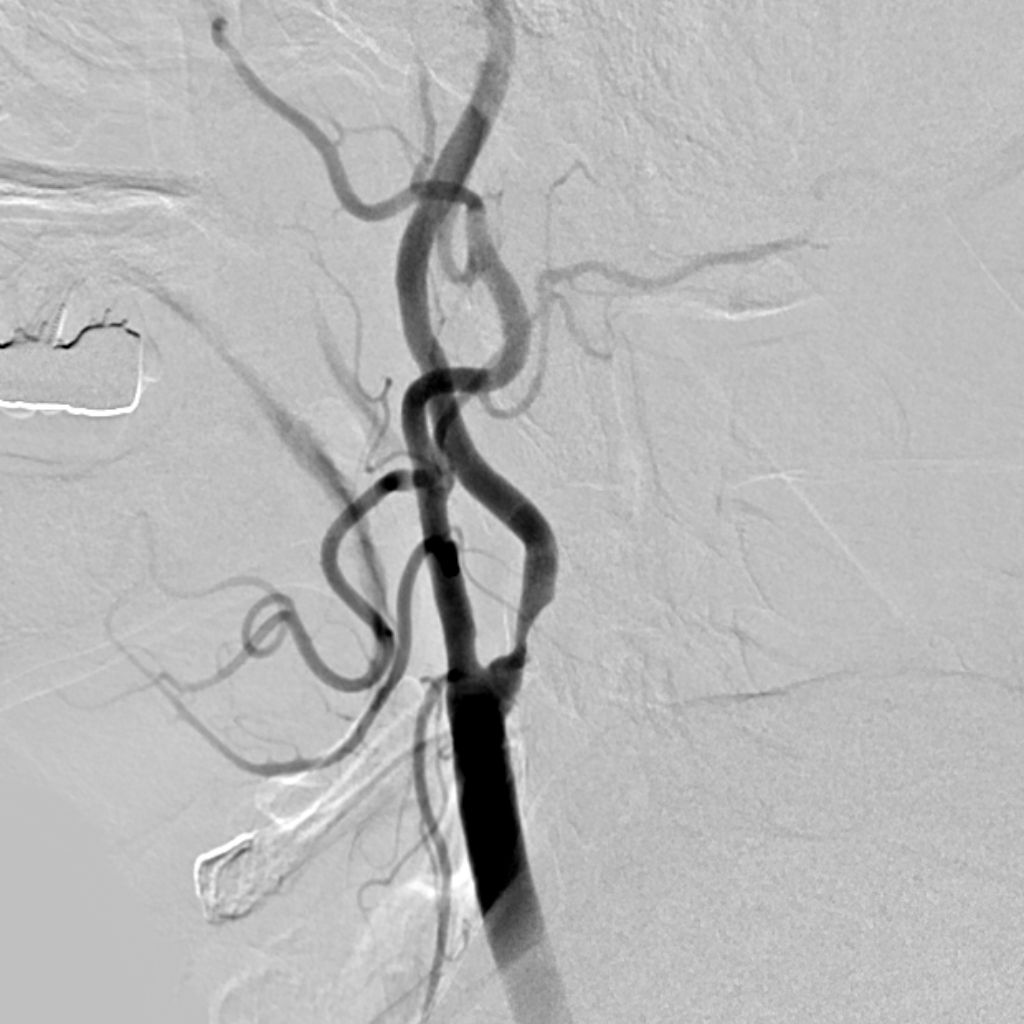

アンギオ装置

肘や太ももの付け根の動脈からカテーテルと呼ばれる細い管を挿入し、造影剤という薬剤を流し込みながら X 線撮影を行うことで、血管の状態や、流れを観察する検査です。

これにより血管にできたコブ(動脈瘤)、血管の狭窄、血管奇形、腫瘍などをより正確に把握し、今後の治療方針の検討を行います。

当院のアンギオ装置Artis zeeはフラットパネル血管造影システムにより、従来装置と比較して約50%の被曝量削減を実現しています。また3D撮影することにより的確な画像を提供することができます。

当院では必要に応じて脳血管内治療(IVR)も行います。

脳動脈瘤のコイル塞栓術や、脳血管の狭窄に対するステント留置術など、IVR(インターベンショナル・ラジオロジー:)と呼ばれる血管内治療に対応しています。

脳血管画像

頸部血管画像